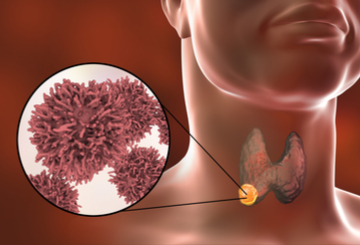

2021年世界世界甲状腺癌大会(WCTC)

2021年07月29日 波士顿

-

2022年世界甲状腺癌大会(WCTC)

2022年04月09日 波士顿

-

2023年世界甲状腺癌大会(WCTC)

2023年06月15日 伦敦

-

2025年世界甲状腺癌大会(WCTC)

2025年07月09日 波士顿